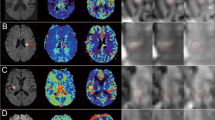

An example of imaging data is shown in Figure 1. The DWI abnormality appears stable at 4 hours after the initial scan, but it increases substantially at 24 hours. The perfusion deficit is much larger than the DWI abnormality, and appears similar at baseline and 4 hours. It becomes smaller at 24 hours, but remains larger than the DWI lesion, indicating relative stability of the region of 'mismatch' over 24 hours. DWI images from each patient at the level of maximum growth are shown in Figure 2. DWI lesions did not change in most patients at 4 hours after baseline. However, most did show a clear increase in volume by 24 hours after baseline.

Diffusion weighted images from all 14 patients. Images were selected at the level of maximum lesion growth for each patient. The baseline, 4 hour, 24 hour and 1 week time points are displayed. The DWI hyperintense abnormalities did not change in most patients at 4 hours after baseline. However, there was an obvious increase in lesion volume by 24 hours after baseline in most patients, as well as at the 1 week time point.

Abnormal DWI and MTT volumes from each patient are shown in Figure 3. At 4 hours after the initial scan, little change in DWI lesion volume is observed in most patients. At this time point only 1 patient (on room air) had more than 50% decrease in abnormal MTT volume, and 1 patient (receiving normobaric oxygen) had more than 30% decrease in abnormal MTT volume. By 24 hours, 5 patients (4 NBO and 1 RA) showed 50% or more decreases in abnormal MTT volume, and 3 other patients (1 NBO and 2 RA) had decreases of more than 30%.

DWI, FLAIR, and Mismatch volumes and NIHSS Scores of individual patients. A. Abnormal DWI lesion volumes at baseline, 4 hours, and 24 hours are depicted in light blue;the 1-week FLAIR lesion volume is depicted in dark blue; and the red bars represent the 'Mismatch' lesion volumes (abnormal MTT lesion volume minus the abnormal DWI lesion volume). Five patients showed evidence for arterial recanalization (arrows, R) on serial MR angiography. One patient had partial recanalization at 4 hours, and four patients recanalized by 24 hours. The time of presentation in hours after stroke onset is shown in parenthesis below each patient number. Patients treated with NBO are marked with asterisks. Notably, a substantial volume of 'Mismatch' was maintained over the 24-hour period of imaging in most patients. B. The NIH stroke scale score for each patient at each imaging time point is displayed.